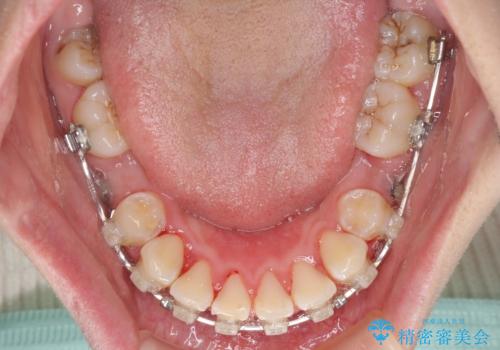

- 矯正装置

- 審美装置

- 骨格的な咬み合わせのズレ、前歯のデコボコとクロスバイトを気にして来院された患者様です。

口元の突出感が若干あり口が閉じにくく、デコボコが強いため、上下左右の小臼歯計4歯を抜歯し、ワイヤー装置による矯正治療を行うこととしました。

治療中に舌の突出癖が改善されず、下顎前歯が著しく前方に突出して反対咬合となってしまう局面がありました。

アンカースクリューを使用しながら舌癖の改善を図り、何とか咬み合わせを改善することができました。